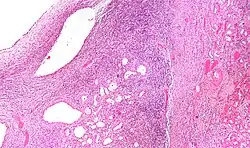

| Micrograph of a cystic nephroma (left of image). Normal kidney is seen on the right. H&E stain. | |